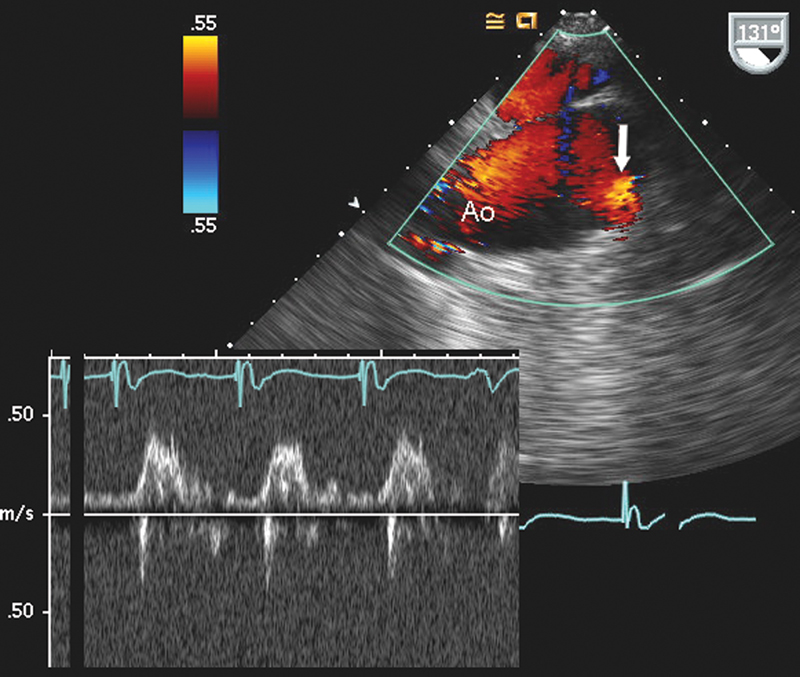

فحوصات تشخيصية لبعض امراض القلب والشرايين التاجية